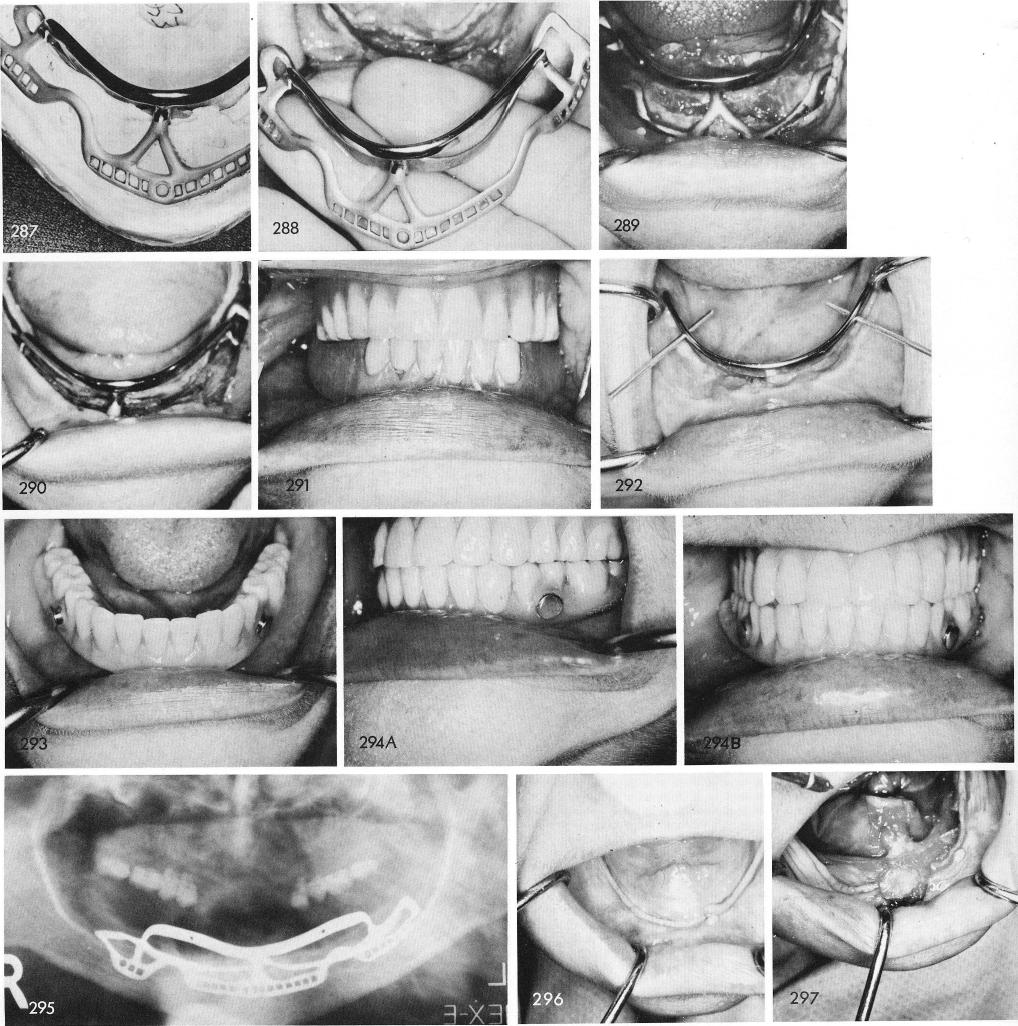

Sometimes implants were made from the very beginning with a bar-superstructure, for sup-porting the implant denture that contained horizontal Lew attachments, figs. 287, 288, 289, 290, 291, 292, 293, 294a,b, 295.

One of the most difficult cases I have ever done is seen in fig. 296. Upon exposing the bone, fig. 297, both inferior alveolar nerves along their entire extent along the body of the mandible as well as both mental neurovascular bundles were exposed, fig. 298. While lifting each nerve up a mandibular canal was created and an inverted T or keyhole was fashioned on the buccal surface of the bone to create a mental foramen, fig. 299. The inferior alveolar nerve was pushed into

1 Inferior alveolar and mental nerves exposed in mandibular ridge